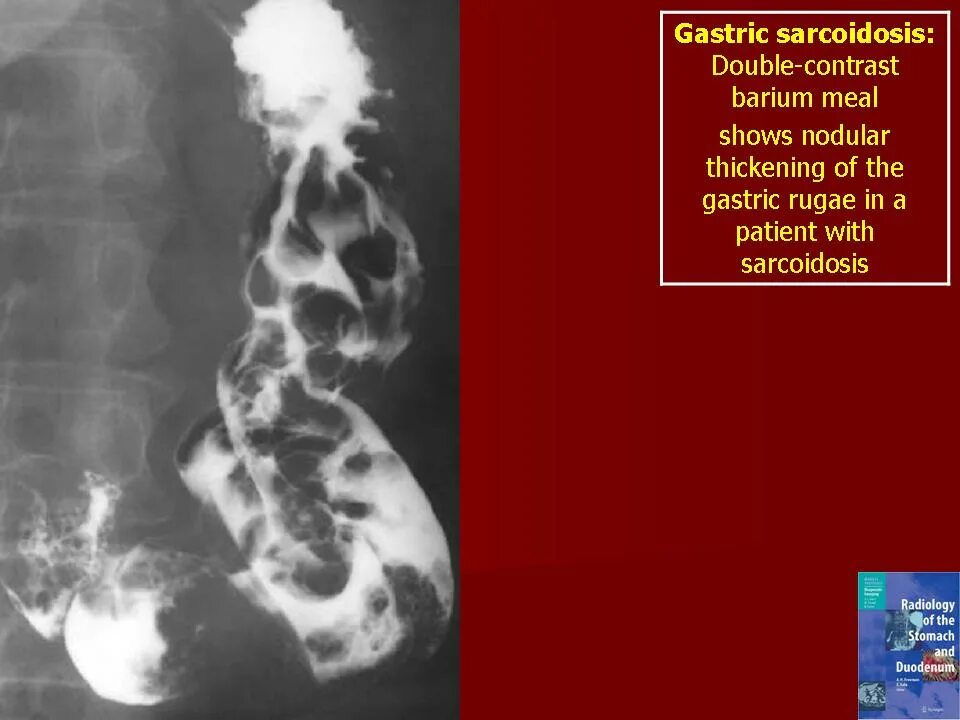

Саркоидоз код по мкб 10 у взрослых